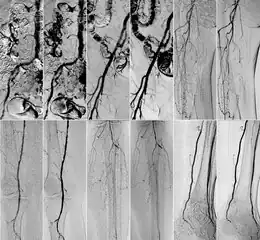

Comparison of kinetic images(KIN) and DSA images in abdominal (top row) and iliac regions (bottom row).

DSA (left) and DVA (KIN, right) image pairs, which were created by administering iodinated contrast agent. From top to bottom: abdominal, iliac, femoral, popliteal and crural regions.